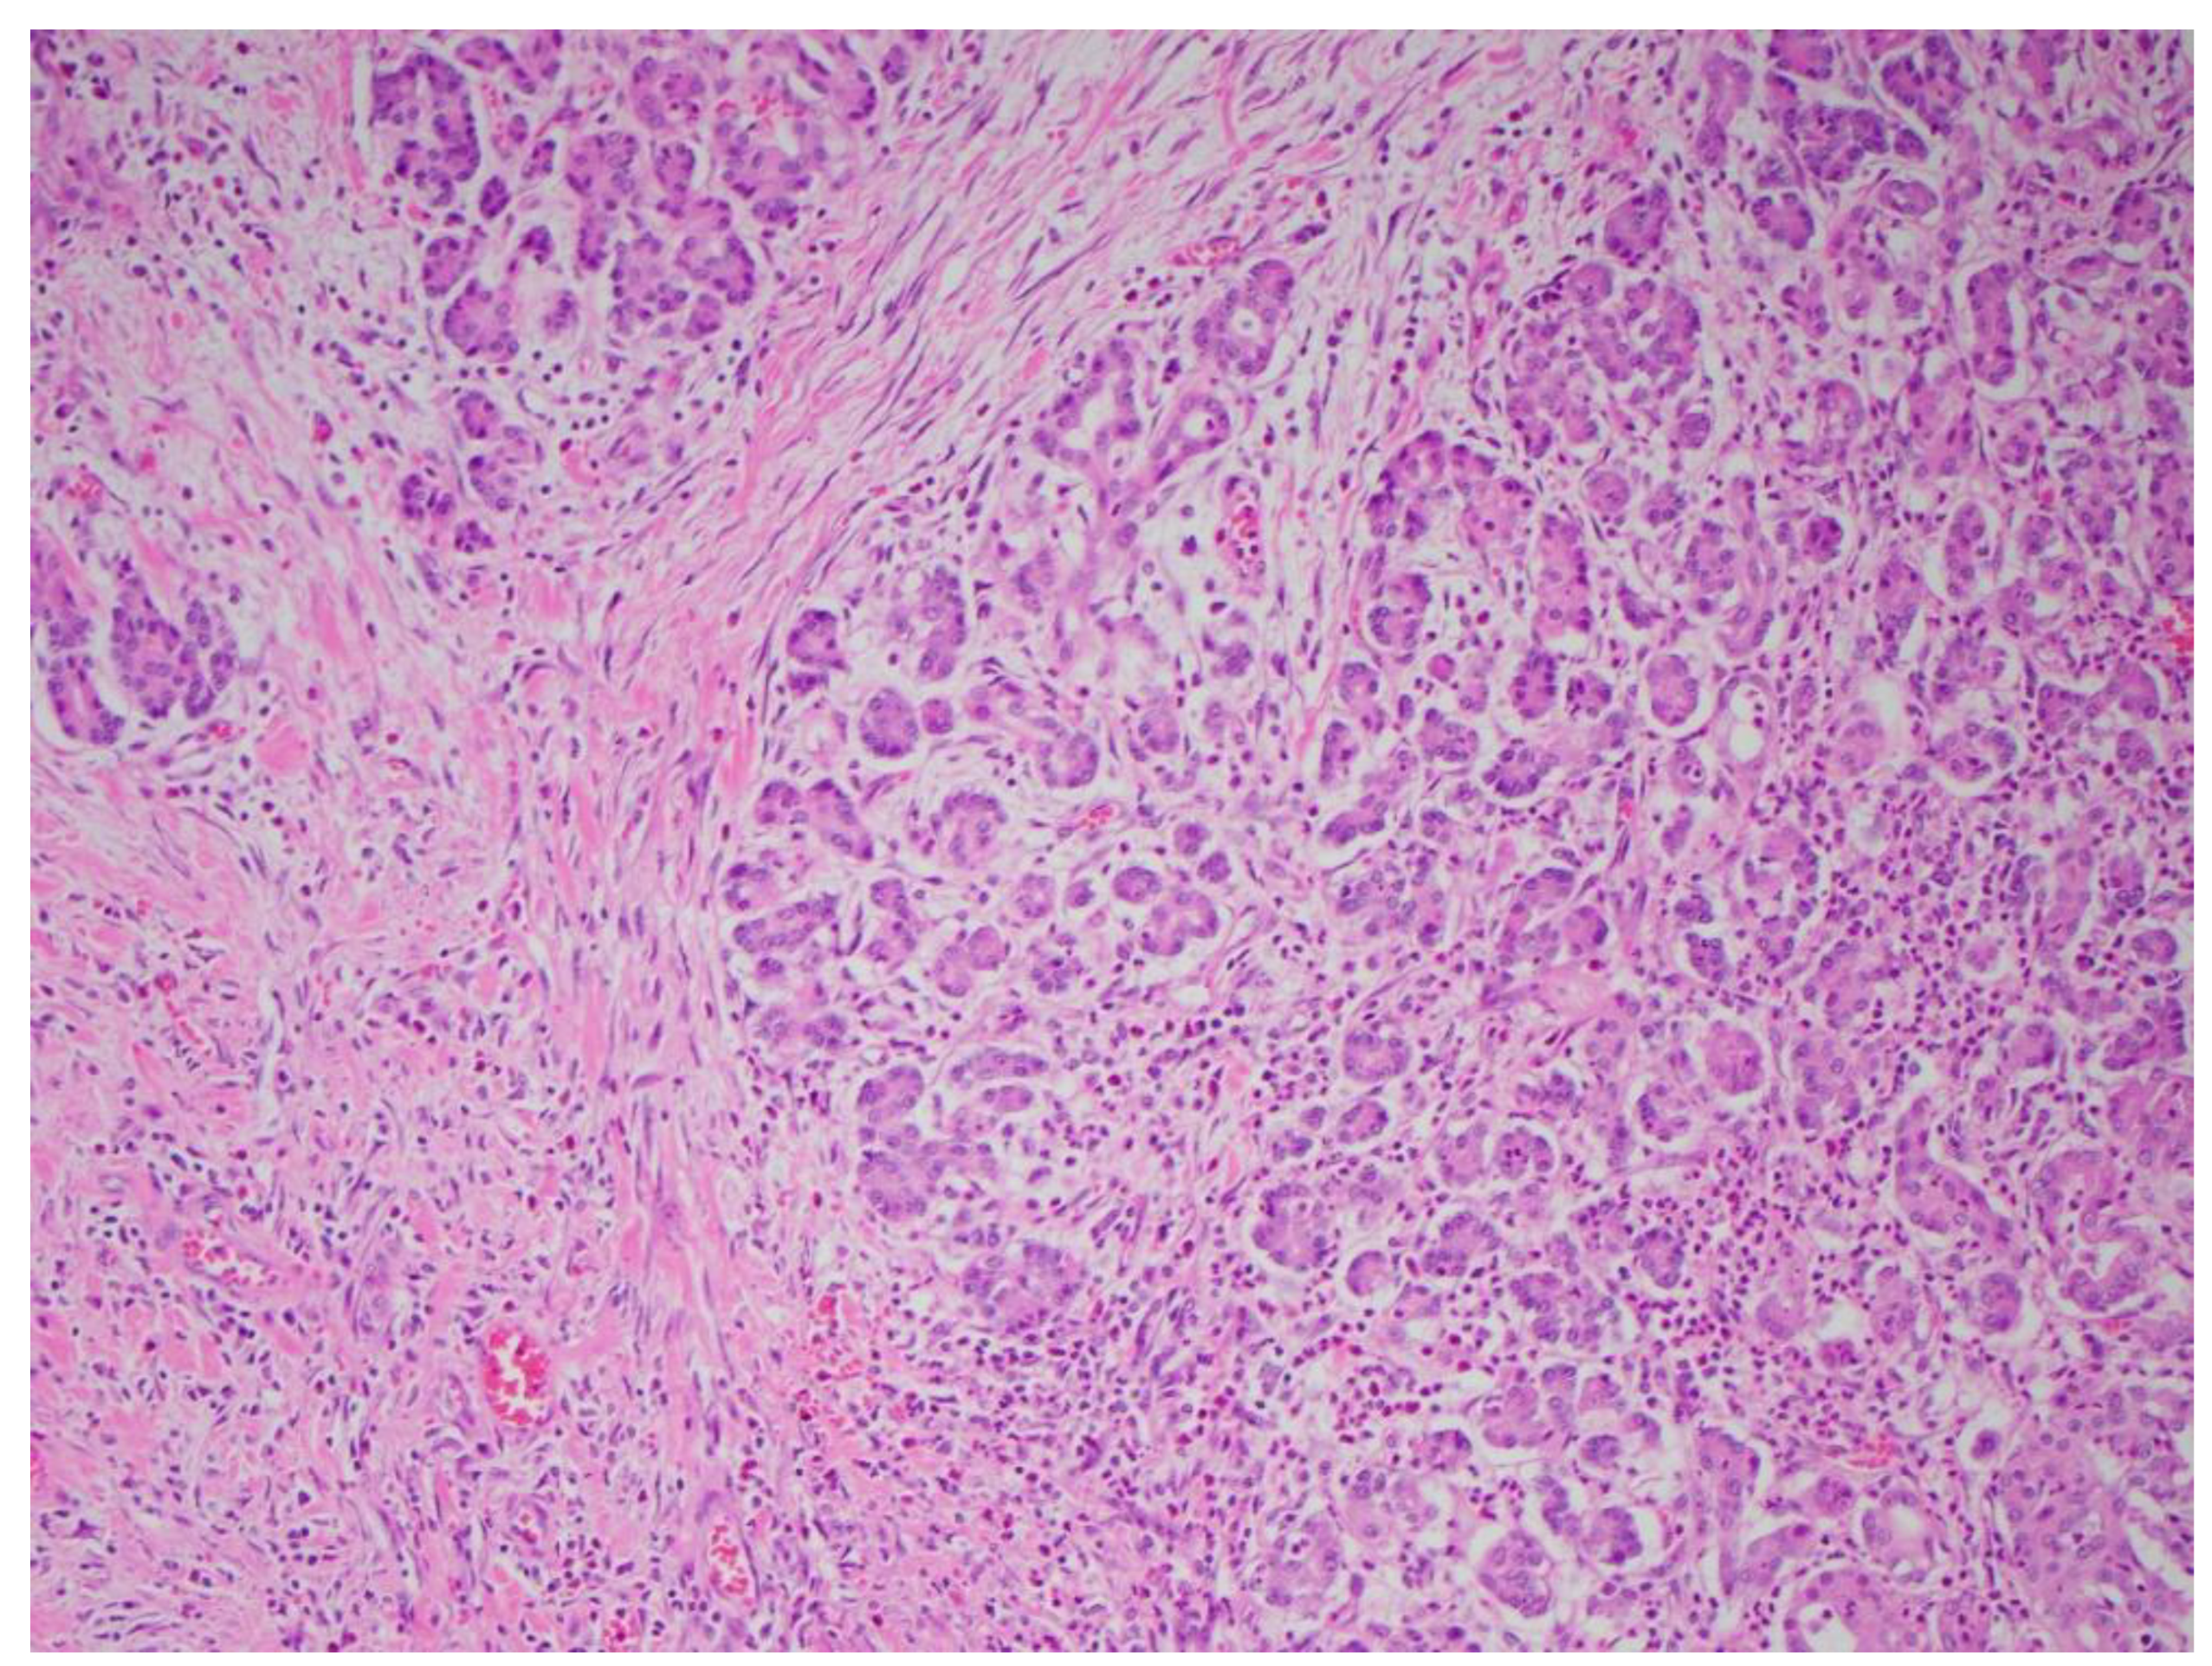

Multiple cytokines mediate a powerful pro-inflammatory immune response, such as tumor necrosis factor-alpha (TNF-a) and interleukins 1a, 1b, 6, and 18, exacerbating the initial pancreatic injury [37]. Pathologically, this appears as inflammation and can also be associated with a hemorrhage at the microscopic level (Figure 2 and Figure 3). The cytokine-mediated inflammatory cascade then extends the inflammatory cascade via lymphatic and systemic circulation into the liver, lungs, heart, kidneys, and gastrointestinal (GI) tract, leading to multi-organ injury [38]. This can cause systemic inflammatory response syndrome (SIRS), an early clinical feature that persists in cases of severe acute pancreatitis. Inflammation and damage to the GI tract can lead to bacterial translocation [39], and the species of bacteria involved are a predictive factor of disease severity, with Enterococcidae most frequently being associated with severe disease [40]. Obesity is also a predictive factor for moderate severity, and it leads to further deleterious effects through adipocyte lipolysis in the pancreas and adipose tissue [41,42] (Figure 2 and Figure 3).

Figure 2. Acute pancreatitis with hemorrhaging (H&E stain, 10×).